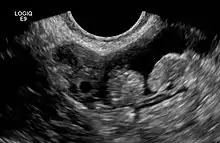

2 epiploic appendages next to an ovary in pelvic ultrasound